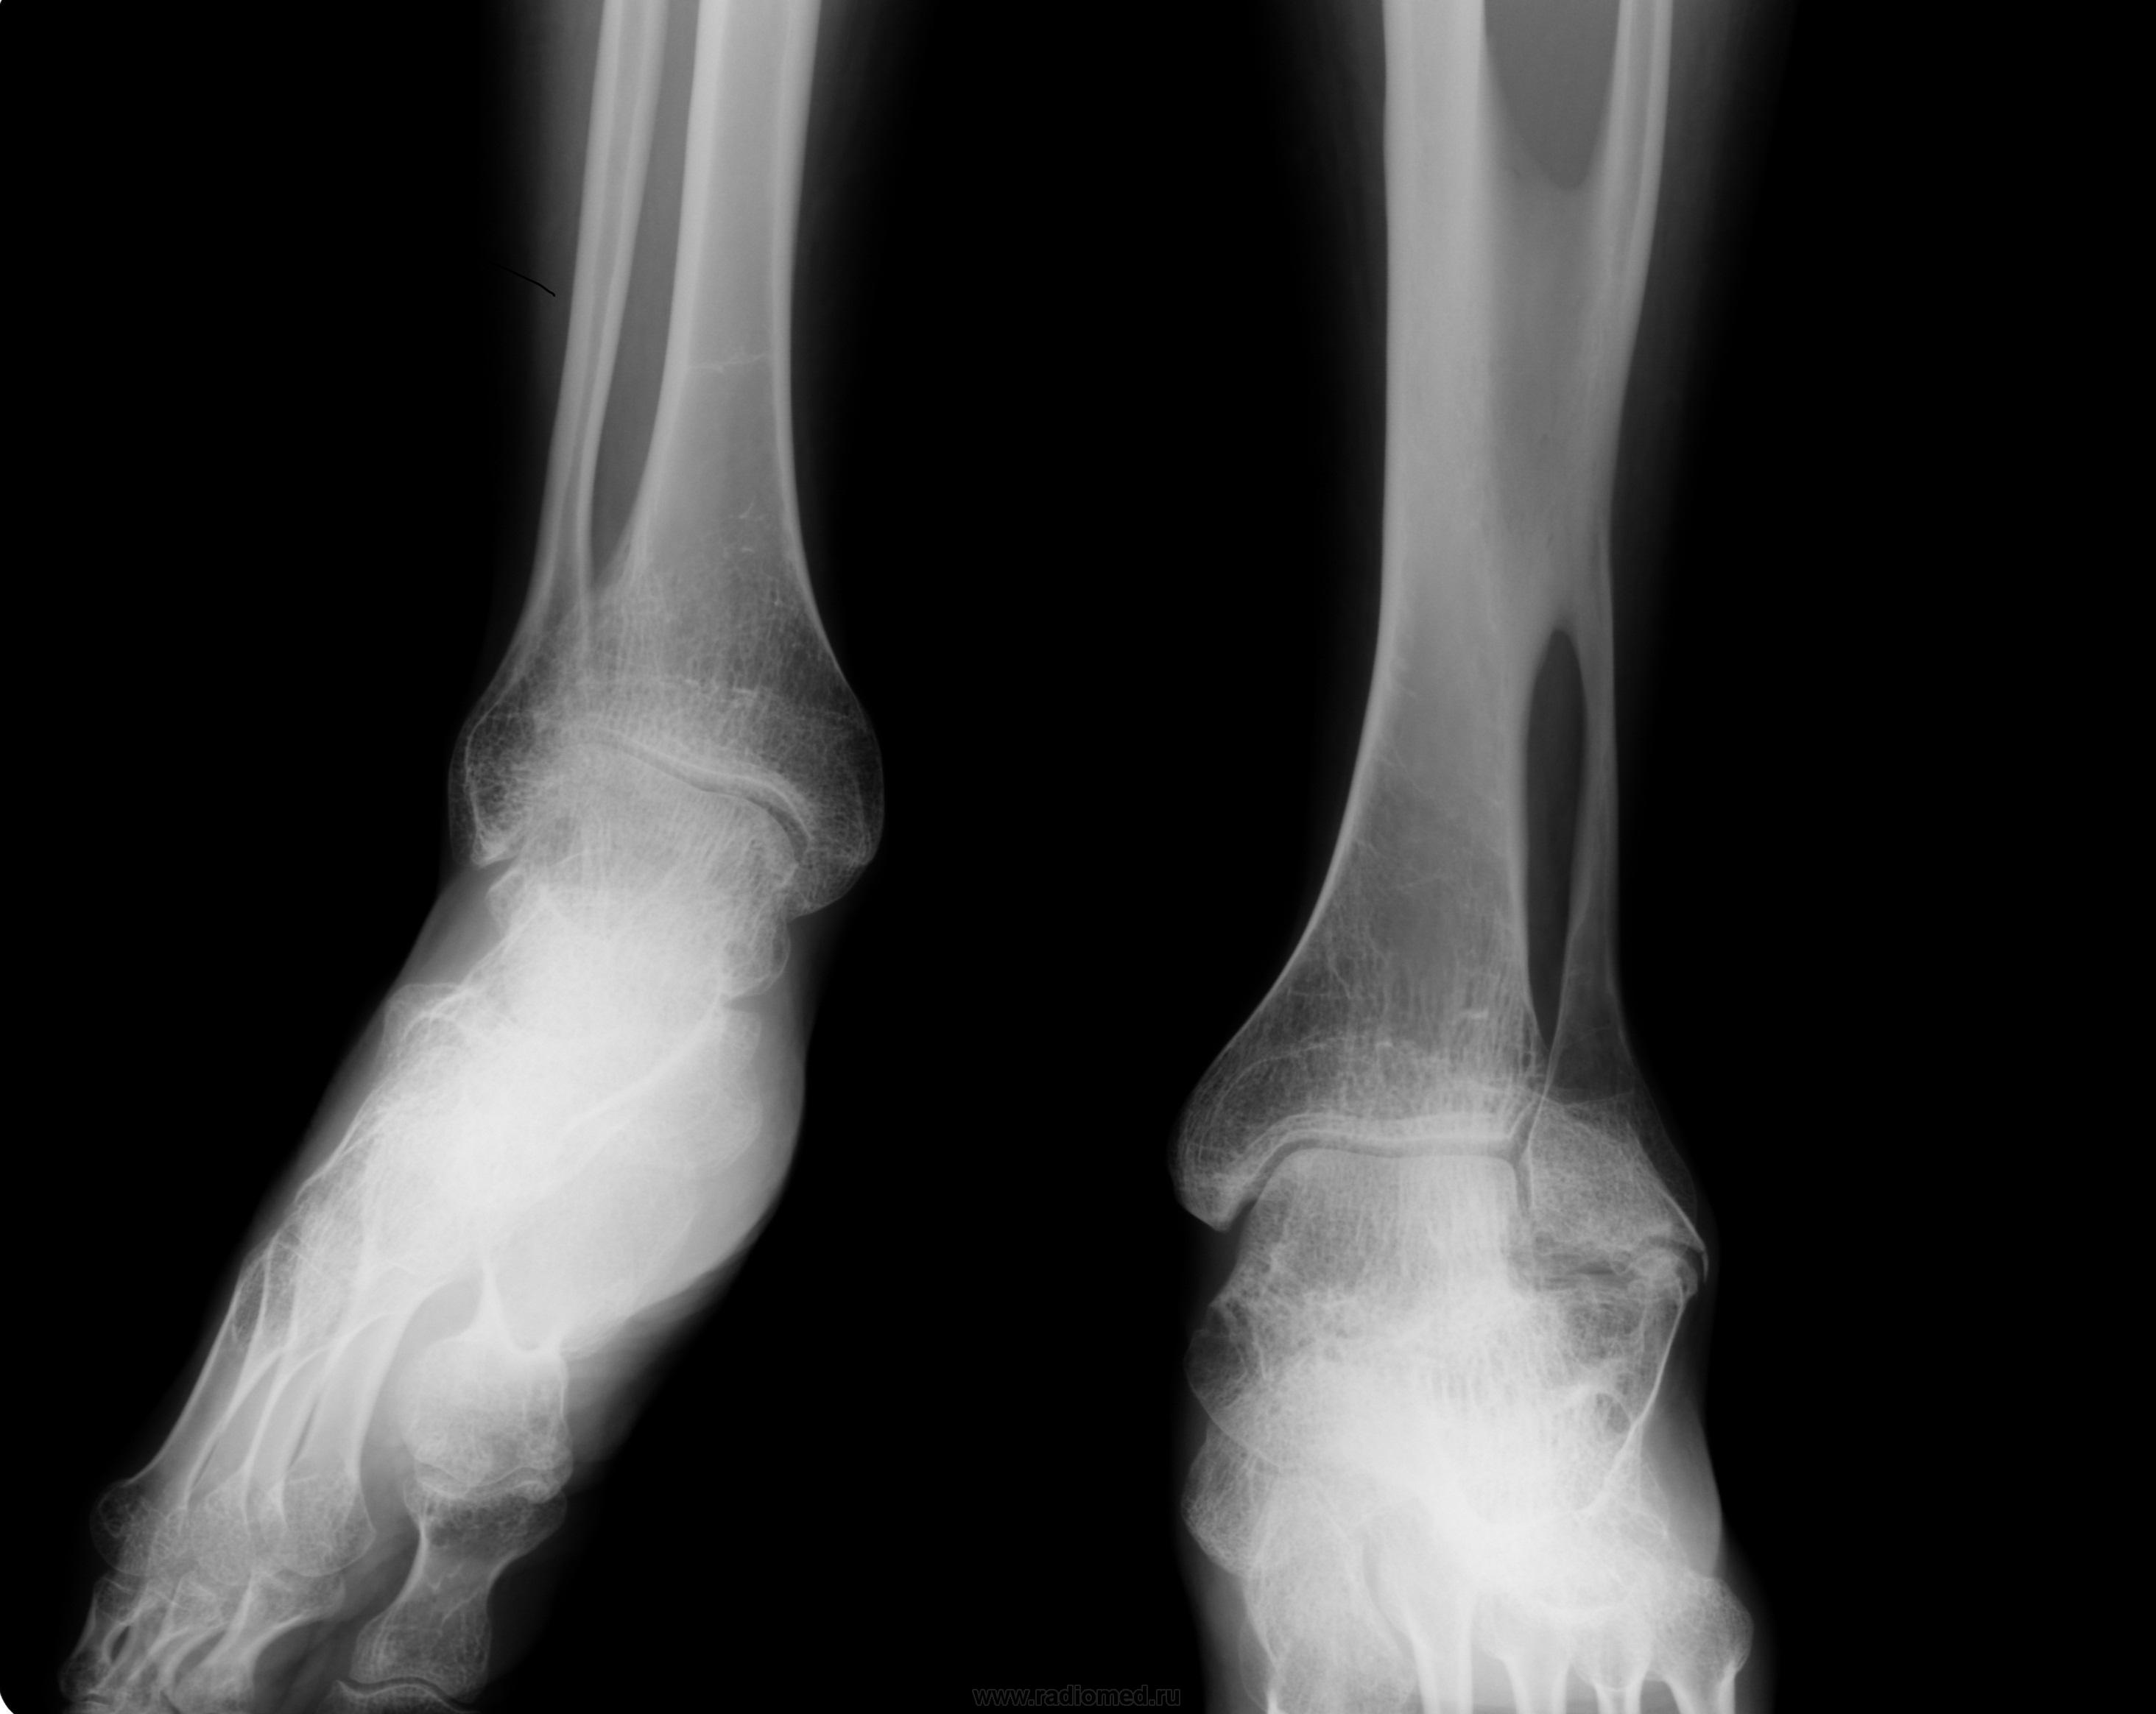

Заключение Главного детского хирурга ДЗ г.Москвы от 02.04.2007 года: Сирингомиелия. Патологический перелом Л2. Кифотическая деформация позвоночника. Радикуломиелопатический синдром. Врожденная сенсорная нейропатия с ангидрозом и спонтанным ангиолизисом. Вальгусная деформация правого коленного сустава на почве остеолизиса дистального мыщелка бедренной кости, нестабильность коленного сустава справа. Плоско-вальгусные стопы.

В неврологическом статусе: Сознание ясное, контактна, ориентирована. Менингеальных знаков нет. Умеренное когнитивное снижение. Несколько эйфорична. Речь дизартричная (неправильный прикус). ЧМН: без патологии. Парезов не определяется. Сухожильные и периостальные рефлексы с рук низкие, без разницы сторон. Коленные и ахилловые отсутствуют. Четких чувствительных нарушений не выявлено. Гипотрофия мышц верхних и нижних конечностей, ягодиц. Грубая деформация правого коленного сустава с формированием ложного сустава, отведением правой голени кнаружи под углом 30-40 град, деформация костей стоп, эквинус с 2-х сторон. Укорочение правой ноги на 15см. ходит с опорой на «мыски». Кифоз шейного отдела. Грубый кифоз поясничного отдела с формированием горба. Сколиоз. Мышечный тонус в верхних конечностях не изменен, в нижних конечностях сни жен, больше справа. Гипермобильность в правом тазобедренном суставе. Тазовые функции: не нарушены.